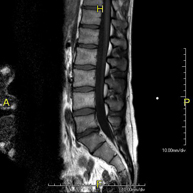

Prova diagnòstica no invasiva que consisteix en l'obtenció d'imatges d'alta definició anatòmica de la columna dorsal, mitjançant l'ús d'un camp electromagnètic i ones de ràdio (amb un emissor i un receptor). No utilitza radiació ionitzant. Indicacions: traumatisme, problemes degeneratius, hèrnies i tumors. - RM Columna Lumbar

Prova diagnòstica no invasiva que consisteix en l'obtenció d'imatges d'alta definició anatòmica de la columna lumbar i sacre mitjançant l'ús d'un camp electromagnètic i ones de ràdio (amb un emissor i un receptor). No utilitza radiació ionitzant. Indicacions: traumatismes, ciàtica, hèrnies discals, tumors i infeccions. - RM de Sacre-còccix